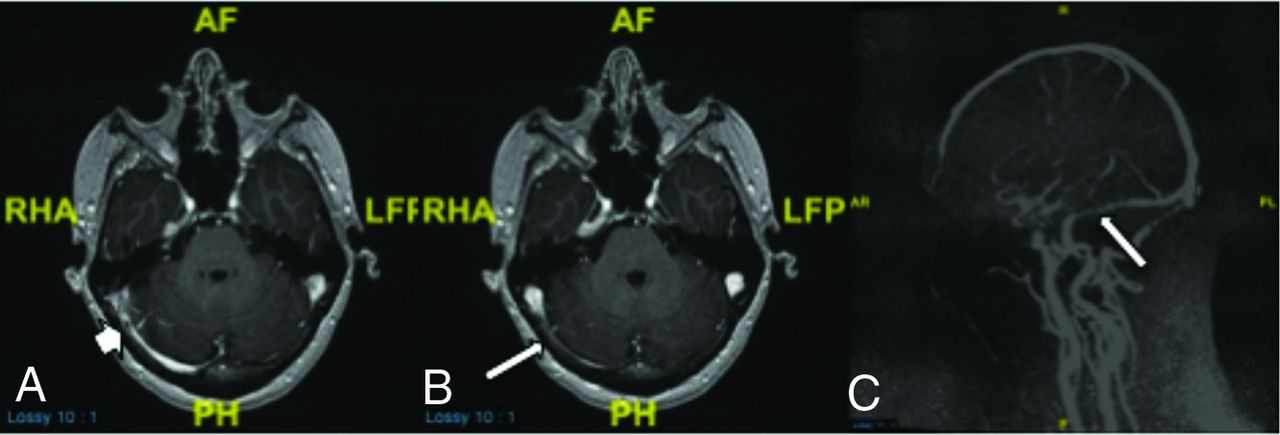

MR images demonstrating focal intrinsic stenosis just proximal to dominant extrinsic stenosis in this patient with idiopathic intracranial hypertension. The short arrow in A demonstrates focal arachnoid granulation. The long arrows in B and C demonstrate a primary extrinsic stenosis pattern. Despite the mixed presence of intrinsic and extrinsic stenoses, this was categorized as primary extrinsic stenosis. RHA indicates right head anterior; PH, posterior head; LFP, left foot posterior; AF, anterior foot; AR, anterior right; PL, posterior left; H, head; F, foot.